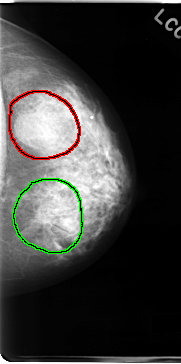

C_0062_1.LEFT_MLO

FILE: C_0062_1.LEFT_MLO.OVERLAY

TOTAL_ABNORMALITIES 2

ABNORMALITY 1

LESION_TYPE MASS SHAPE IRREGULAR MARGINS ILL_DEFINED

ASSESSMENT 4

SUBTLETY 2

PATHOLOGY MALIGNANT

TOTAL_OUTLINES 1

BOUNDARY

ABNORMALITY 2

LESION_TYPE MASS SHAPE LOBULATED MARGINS CIRCUMSCRIBED

ASSESSMENT 3

SUBTLETY 5

PATHOLOGY BENIGN